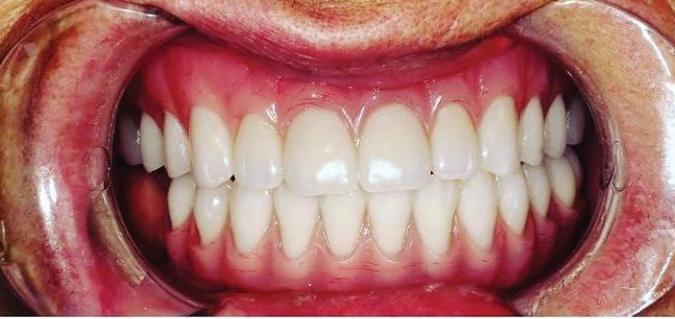

New Solutions For Dentures and Dental Implants

Dentures are a good replacement option for patients who are missing all of their teeth, but only if they fit well.

How Can Dentures Fit Well For a Long Time?

Dental implants can be placed under the denture. Implants have offered the possibility of fully replacing teeth for over 30 years and are very safe and effective. When you make the denture stable by “snapping” it onto dental implants, you can provide a better level of comfort for the denture-wearer, and create new strength for eating the foods patients love.

Dental implants are very much like your natural teeth. They are quite easy to get used to, and they can reduce the amount of stress to the bone and jaw by helping provide an anchor for support. The implant acts as a natural root to help prevent additional bone deterioration and helps to deliver long lasting function.

Discover the difference dental implants can make for you. Schedule an appointment today!

– Dental Implants To Restore Your Beautiful Smile

Our patients mean the world to us (and they love to refer to us as friends and family). My team works together to ensure your visit is enjoyable, and that your treatment is gentle and pain-free. We are deeply committed to help you prevent and treat periodontal (gum) disease, and to enhance your smile to improve your overall health.